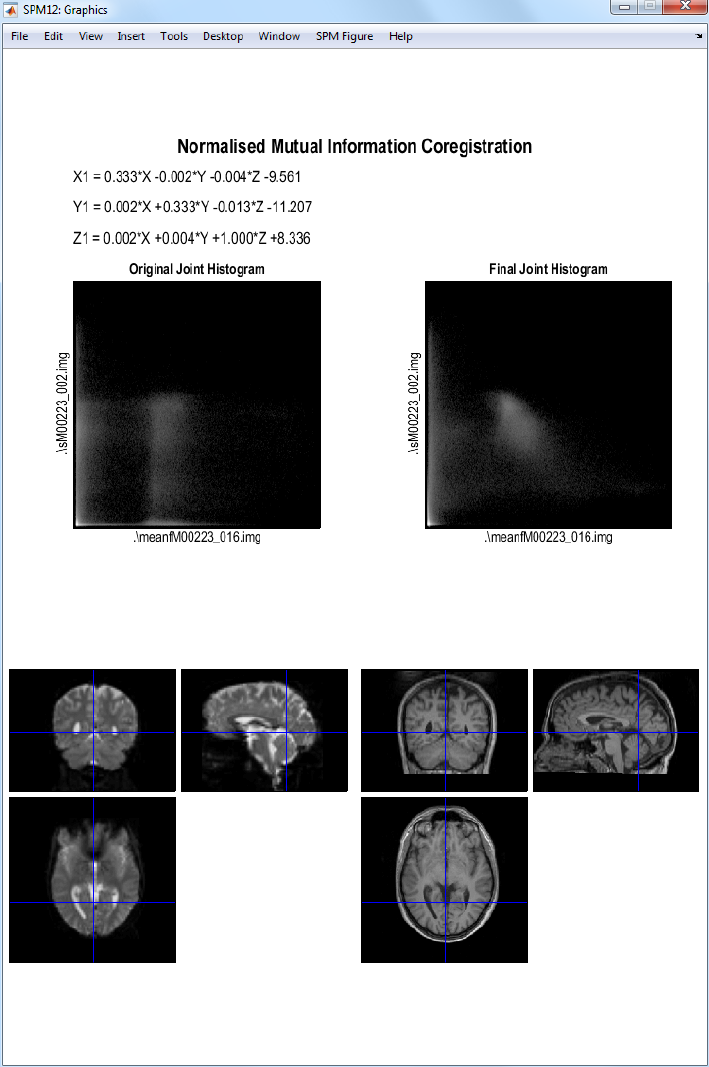

30.2.2 Coregistration ..................................223

31.1.4 Coregistration ..................................248

42.7.3 Coregistration of mean EPI (fMRI) to T1 (sMRI) ..............422